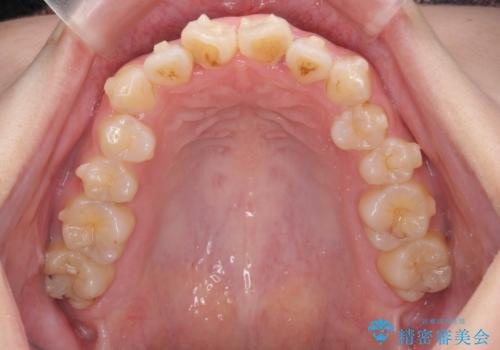

前歯のねじれをマウスピース矯正インビザラインで治療

- 長年気になっている、前歯のねじれの矯正治療を希望され来院されました。

十分にマウスピース矯正インビザラインで治療が可能と判断し、治療を進めることとしました。

長年気になっていた前歯のねじれが、ワイヤーをつけることなく矯正を行うことができ、大変喜んでいただくことができました。